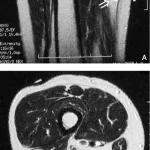

縫工筋(5. Sartorius m.)のすぐ深部には, 大腿動脈と静脈(4. Femoral a and v.)が走行しており, その深部には, 内側広筋(2. Vastus medialis m.)があります.

すなわち, 縫工筋と内側広筋が切れて, 大腿骨に達しているキズでは, 大腿動脈と静脈が切れている可能性が高いです.

大腿部内側の筋肉(縫工筋, 内側広筋)が切れて, 大腿骨にまで達していました.

部位と深さからは, 大腿動静脈が切れている可能性が高いと判断し, 血管外科での手術が必要と判断.